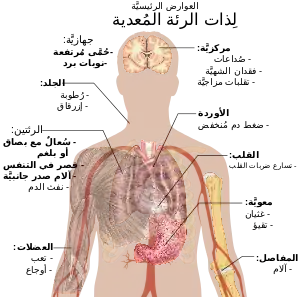

العلامات والأعراض

كثيرًا ما يشكو المصابون ذات الرئة من السعال الرطب والحمى التي يصاحبها القشعريرة وضيق النفس وألم صدري حادّ أو طاعن أثناء التنفس العميق وازدياد سرعة التنفس.[14] وقد يكون الارتباك هو أكثر الأعراض وضوحًا لدى المسنين.[14] أما الأعراض والعلامات النمطية لدى الأطفال الذين يقل عمرهم عن خمسة أعوام فهي الحمى والسعال والتنفس السريع أو الصعب.[15]

الحمى ليست مميزة تمامًا، فهي تحدث في العديد من الأمراض الشائعة الأخرى، وقد تكون غائبة لدى الذين يعانون من مرض شديد أو سوء التغذية. بالإضافة إلى ذلك، كثيرًا ما لايكون السعال موجودًا لدى الأطفال الذين يقلّ عمرهم عن الشهرين.[15] ومن العلامات والأعراض الأكثر شدّة فقد تتضمن: الجلد المائل إلى الزرقة وتناقص الشعور بالعطش واختلاجات وتقيؤ مستمر وارتفاع شديد في درجات حرارة وتراجع درجة الوعي.[15][16]

تشكو حالات ذات الرئة الناتجة من عدوى بكتيرية وفيروسية بأعراض متماثلة.[17] ترتبط بعض الأسباب بخصائص سريرية تقليدية، ولكنها غير متميزة. ذات الرئة الذي يحدث بسبب البكتريا الفيلقية (Legionella) قد يكون مصحوبًا بألم في البطن أو إسهال أو ارتباك.[18] في حين أن ذات الرئة الذي يحدث بسبب العقدية الرئوية يترافق بقشع صدئي اللون.[19] في حين أن ذات الرئة الذي يحدث بسبب كليبسيلا (Klebsiella) قد يرافقه قشع مدمى كثيرًا ما يوصف بأنه يشبه هلام الكشمش (التوت البري).[13] القشع المدمى (والذي يعرف باسم نفث الدم) قد يحدث أيضًا في حالات السل وذات الرئة بالجراثيم السلبية الغرام والخراجات الرئوية بالإضافة إلى حدوثه أكثر شيوعًا في التهاب القصبات الحاد.[16] أما أعراض ذات الرئة "بالمفطورات" فقد تكون تضخم العقد اللمفية في الرقبة والألم المفصلي والتهاب الأذن الوسطى.[16] أما التهاب الرئة الفيروسي فيترافق بالأزيز أكثر من التهاب الرئة البكتيري.[17]